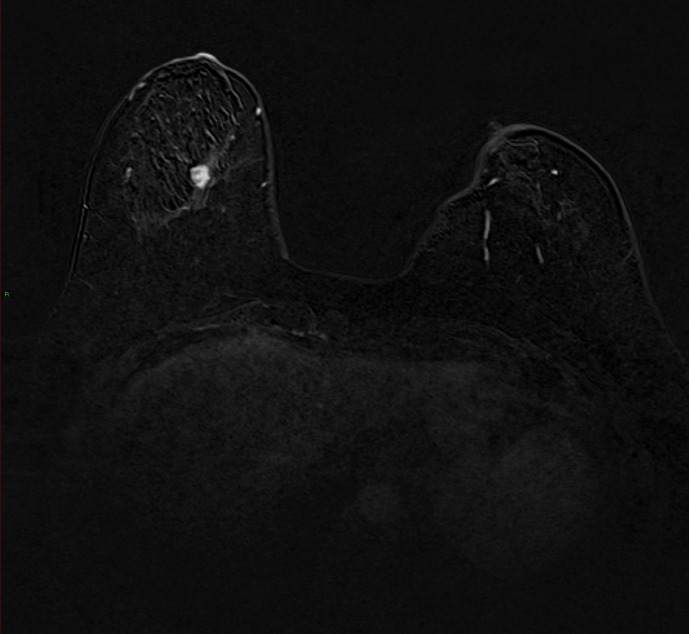

A number of COVID-19 vaccines have been approved worldwide to help tackle the pandemic. As with many vaccines, this causes a reactive axillary lymphadenopathy which can mimic potentially metastatic disease in a breast screening patient. It is therefore important to be aware of this side-effect of the vaccination when evaluating the axilla in a breast screening patient. We present a case of biopsy-proven unilateral reactive axillary lymphadenopathy in a high risk BRCA carrier following administration of the Astra Zeneca vaccine.

Abstract Image